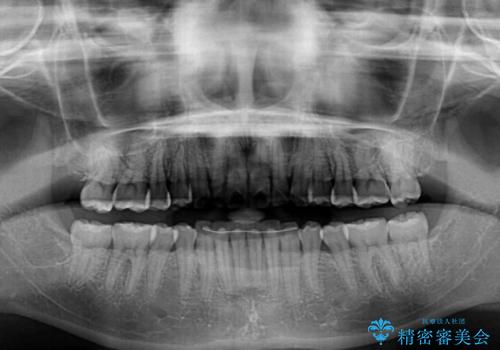

ワイヤー矯正へ変更してからはあっという間に治療が進み、1年弱で終えることができました。

- 矯正治療後の保定が不十分だと後戻り(元の位置に戻ろうとする動き)をします